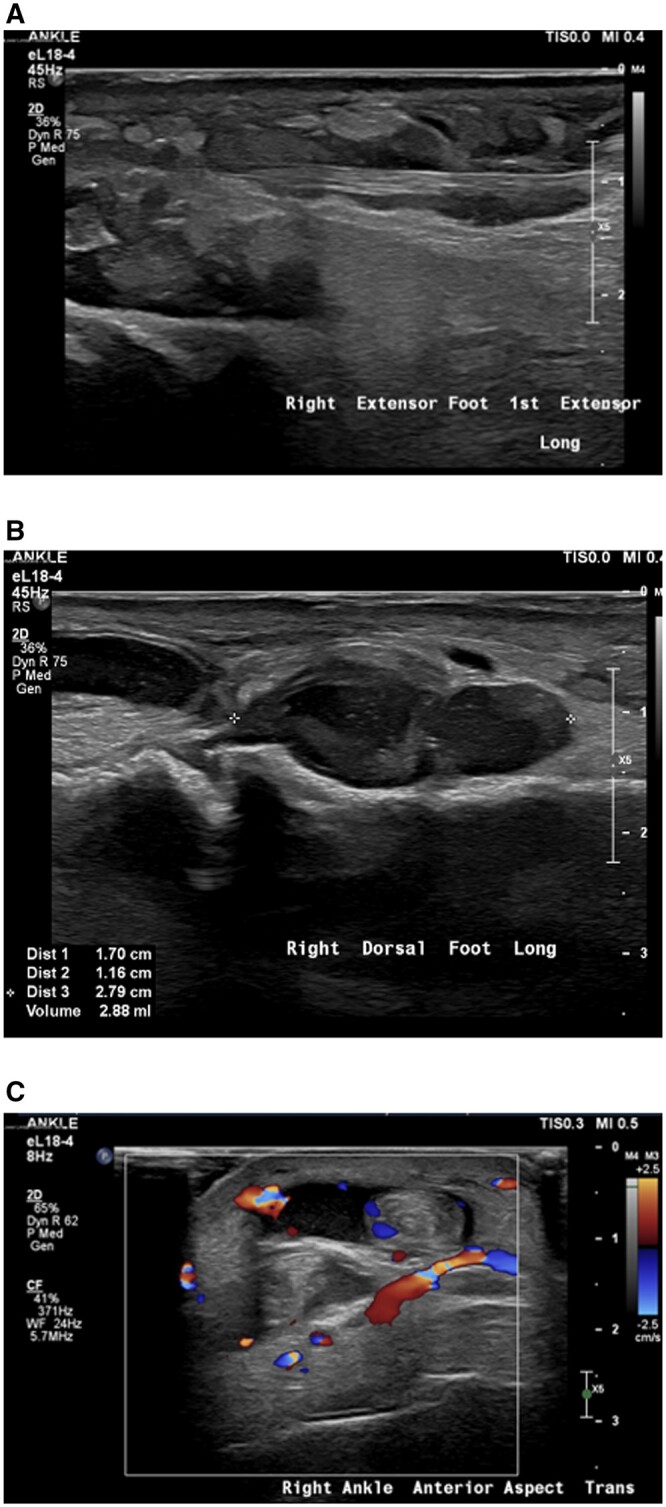

严重胰腺炎后逆行胆管造影(ERCP)是罕见的发生。更罕见的是,在ercp诱导的胰腺炎后可能出现的其他非胰腺症状,如胰腺炎和多发性关节炎。这种症状的组合被认为是胰腺炎、胰膜炎和多关节炎综合征(PPPS)。PPPS典型表现为红色皮下结节,主要发生在下肢。在某些情况下,病情可能进展到骨骼,引起髓内脂肪坏死/骨梗死。关节并发症包括多关节炎,影响大小关节。PPPS往往发生在临床胰腺炎高峰后3-6周。在本报告中,我们提出了一例PPPS作为ERCP后并发症发生的病例。由于菌血症和真菌血症的存在,这一特殊病例进一步复杂化,导致随后发展为多灶性骨髓炎。本报告中包含的医学影像提供了整个临床过程的全面概述,从最初的术后并发症和胰腺炎开始,随后使用超声和MRI进行多模态成像,描绘了睫状体炎,最后说明了多灶性骨髓炎的发展。本病例为探讨和了解胰腺炎相关的两种罕见并发症:PPPS和多灶性骨髓炎提供了机会。

Severe pancreatitis following retrograde cholangiopancreatography (ERCP) is an infrequent occurrence. Even rarer are the additional non-pancreatic symptoms that can emerge after ERCP-induced pancreatitis, such as panniculitis and polyarthritis. This combination of symptoms is recognized as the pancreatitis, panniculitis, and polyarthritis syndrome (PPPS). PPPS typically manifests as reddish subcutaneous nodules, primarily in the lower extremities. In some cases, the condition may progress into the bones, causing intramedullary fat necrosis/bone infarcts. Joint complications involve polyarthritis and affect both small and large joints. PPPS tends to develop 3-6 weeks after the peak of clinical pancreatitis. In this report, we present a case of PPPS that occurred as a complication following ERCP. This particular case became further complicated by the presence of bacteraemia and fungaemia, leading to the subsequent development of multi-focal osteomyelitis. The medical imaging included in this report provides a comprehensive overview of the entire clinical course, starting from the initial post-procedural complication and pancreatitis, followed by multi-modal imaging depicting panniculitis using ultrasound and MRI, and finally illustrating the development of multi-focal osteomyelitis. This case serves as an opportunity to explore and understand 2 rare complications associated with pancreatitis: PPPS and multi-focal osteomyelitis.